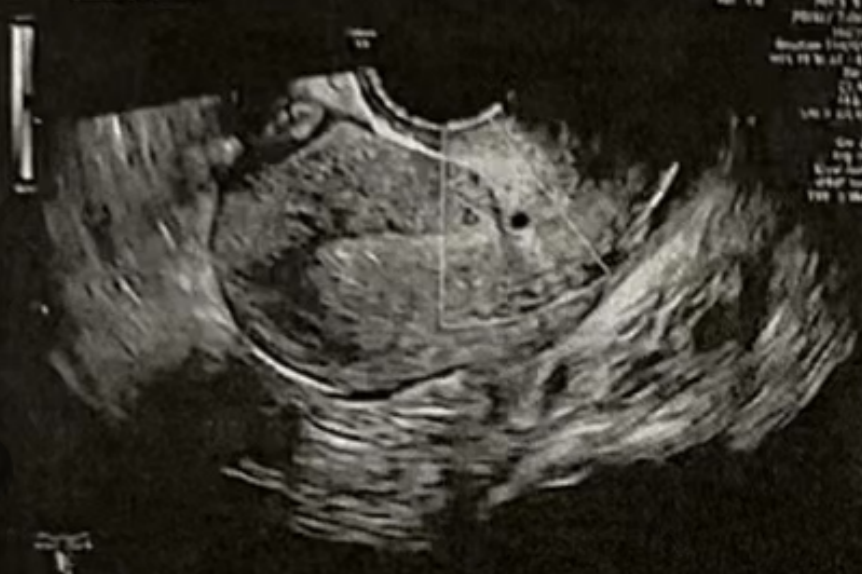

子宫内膜厚度:9.3-10 毫米

- 有粘液滞留在腔内,从峡部瘢痕延伸至子宫底

- 双卵巢无囊肿

- 计划在胚胎移植前重复超声检查以冲洗峡部瘢痕

• Pre-Irrigation灌洗后: